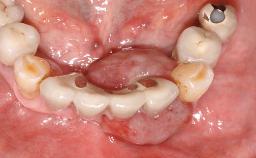

Retreatment of a Patient with Multiple Biological and Technical Complications and Failures

A 66-year-old patient presented because of retention loss of the tooth-supported FDP in the right maxilla (x-13-x-11). The mandibular full-arch implant-supported reconstruction (x-i34-i33-x-x-x-x-i43-i44-x) had suffered extreme wear. His medical history revealed high blood pressure, controlled with anti-hypertensive medication. The patient was a light smoker (2 to 3 cigarettes per day). The existing reconstructions had been performed alio loco about five years previously. That treatment had taken an extensive amount of time, and as early as during the fabrication of the reconstructions, multiple complications had occurred with the provisionals.